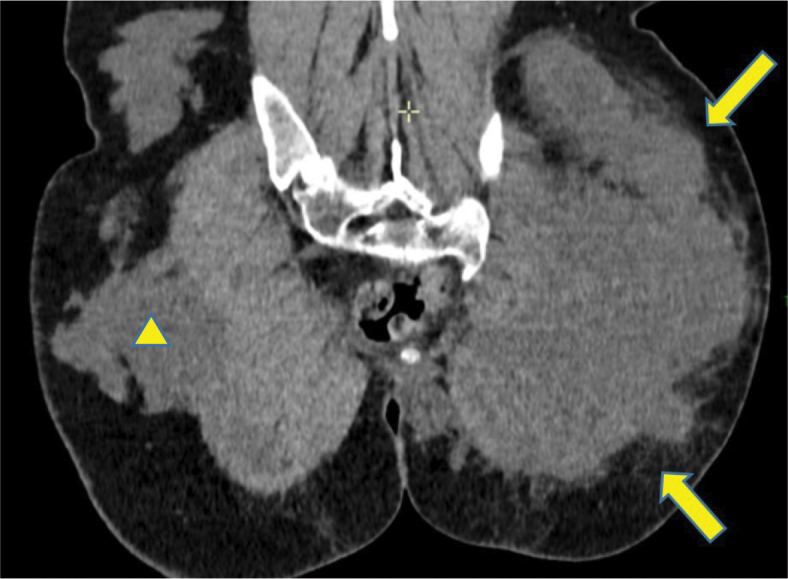

Teaching point: To highlight the potential complications associated with AQUAfilling injections, emphasizing the importance of early detection and proper management.

Abstract Image